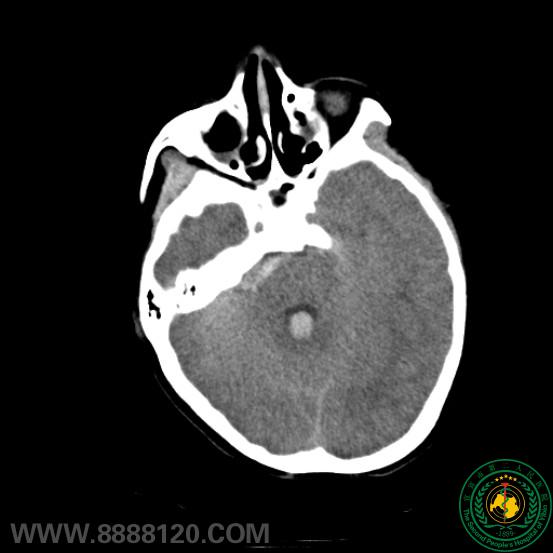

患儿11岁  以突发头痛伴意识障碍入院  头颅CT示蛛网膜下腔出血(桥前池为著),脑积水,脑室积血。